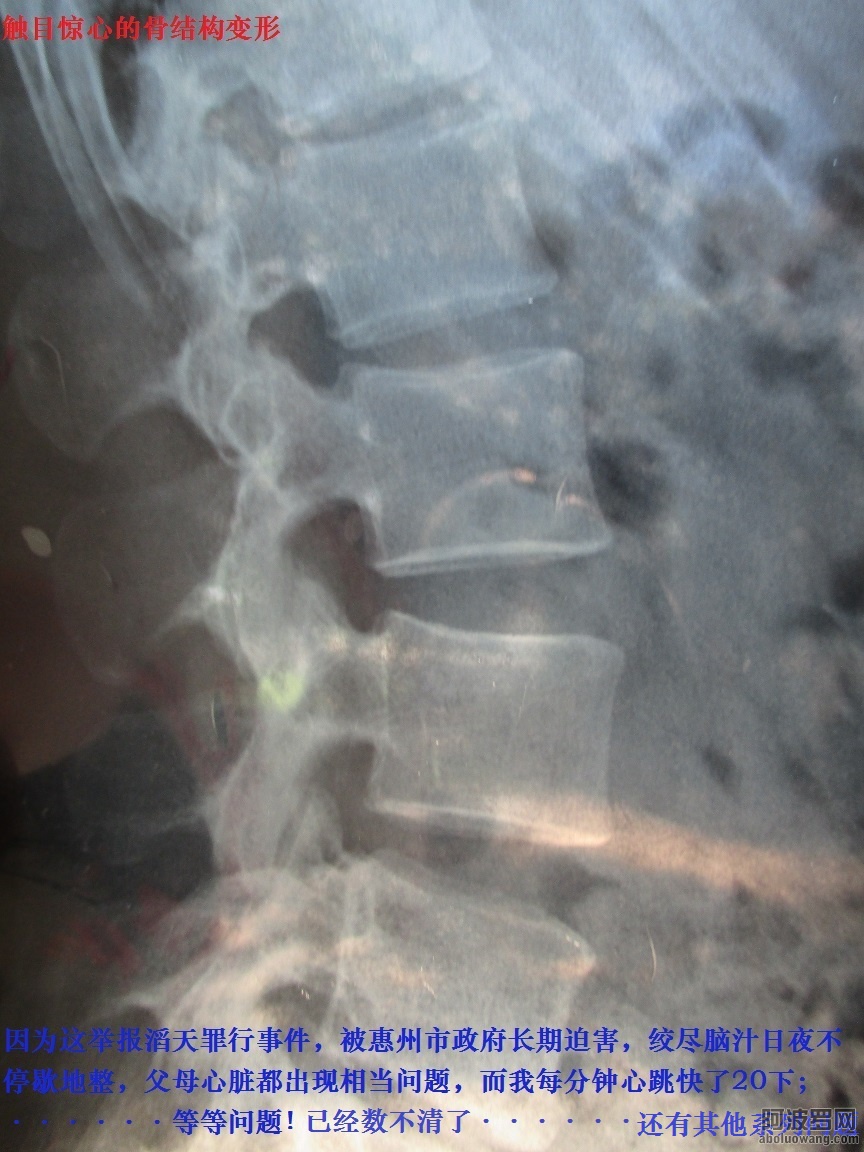

在行程中每一天都中暑,骨架變形老化、異位、脫落···本身就在不斷的發炎發燒;脊柱彎曲了不能動就在馬路旁邊躺下壓正一點,中暑了迷迷糊糊就灌涼水,清醒一點再上路。

因爲這事件,被惠州市政府長年累月絞盡腦汁日夜不停歇地整,父母心髒都出現相當問題,我母親也相續住院了,心髒出現病患,她特別向我說明是惠州政府長期整她産生的;●而我每分鍾心跳加快20次或者以上,明顯感到心悸、胸悶、不適···【惠州市政府長年累月精神虐待暴力摧殘,導致舉報滔天罪行者全家人患心髒病】

2:惠州市政府長期暴力摧殘精神虐待、殘酷迫害導致舉報人全家都患了心髒病。